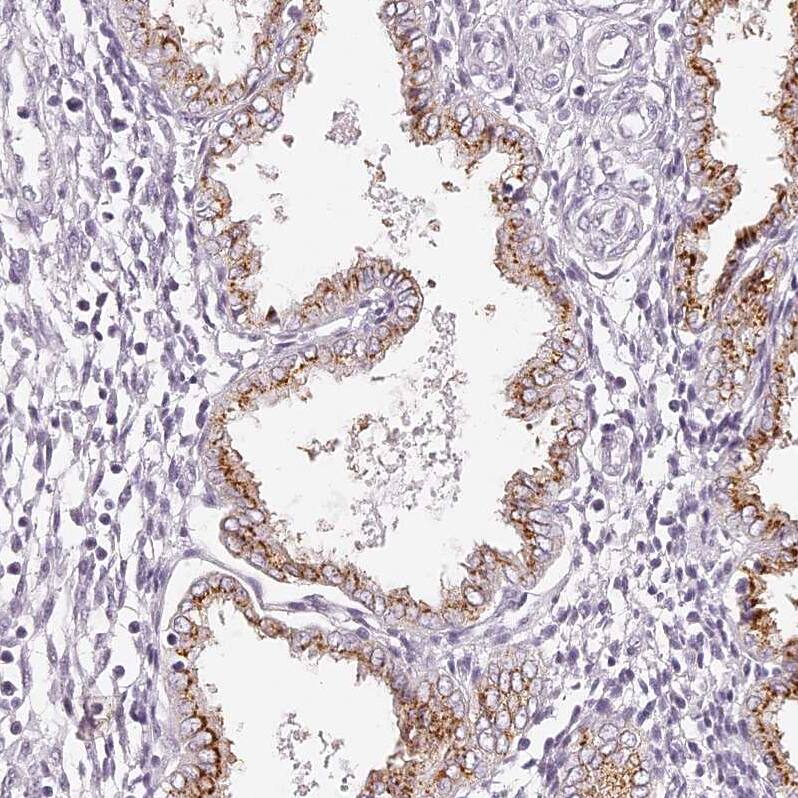

Staining of human prostate shows strong cytoplasm granular positivity in glandular cells.